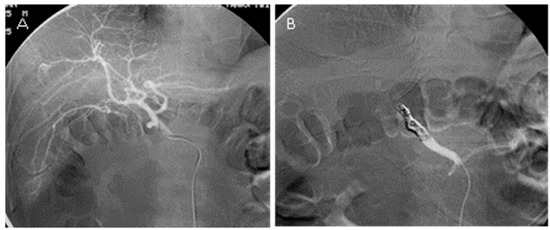

2.2. TAE Procedure